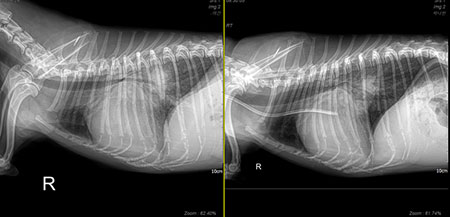

그래서 이 아이는 어떻게 되었을까? 아이의 수술 전 방사선부터 수술 10일 차의 방사선 사진은 이렇다[그림 5, 6].

이렇게 되었다. stage D 환자에서 이뇨제를 고용량으로 쓰고, 신수치가 많이 오르고, 핍뇨나 무뇨까지 갔던 환자들에게 V-clamp 수술을 해놓으면 어떻게 될까?

나는 clamp 수술을 한 환자들에게 수술 후 수액을 거의 주지 않는다. 진통제와 진정제 정도만 혈관으로 주고, 나머지는 음수로 보충한다. 놀랍게도 환자는 2~3일간 아주 많은 양의 뇨를 내보낸다.

신수치는 수술 이후로 빠르게 떨어진다. 심장을 작게 유지하기 위해 전부하를 줄이려고 이뇨제를 수술 전과 비슷하게 혹은 더 많이 쓰더라도 신장은 뇨를 잘 만들고, 신수치는 며칠에 걸쳐 정상까지 떨어진다.